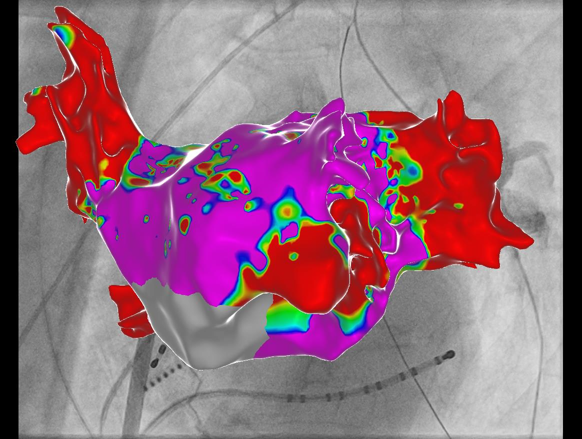

Als Radiofrequenzablation wird die gezielte Behandlung von Gewebe mit Hitze bezeichnet. Vorangeht die Erstellung einer “elektrischen Landkarte” Ihres Herzens unter Verwendung eines 3D-Navigations-Systems. Aufgrund moderner Röntgen-Integration können die Eingriffe weitgehend strahlenfrei, in speziellen Fällen - etwa bei schwangeren oder stillenden Patientinnen - auch gänzlich strahlenfrei erfolgen.

Anhand der elektrischen Landkarte kann die Therapie ganz individualisiert geplant und zielgerichtet und schonend durchgeführt werden. Im Gegensatz zur PFA Technologie können hier auch Therapieziele außerhalb der Lungenvenen in gleicher Sitzung behandelt werden.

Ein dreidimensionales medizinisches Modell des Herzens mit farbiger Oberflächenanzeige auf einem Röntgenbild. 3D Navigation einer Vorhofflimmerablation

Ultra-hochauflösende Mapping-Verfahren

Besondere Fälle bedürfen besonderer Ansätze - wir verwenden modernste, hochauflösende Mapping-Katheter um das genauste Bild aus ihrem Herzen zu erhalten. Hierbei kommen zunehmend auch KI-gestützte Algorithmen zur Datenaufarbeitung zum Einsatz. Die so erstellten extrem detaillierten elektrischen Landkarten helfen dabei, die zugrunde liegende elektrische Erkrankung besser zu verstehen und gezielter zu behandeln - die Verödung wird damit effizienter und erfolgreicher